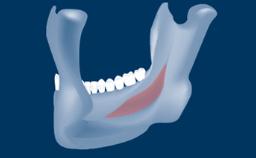

• intraoperative complications of lateral window sinus floor elevation

• intraoperative complications of transcrestal sinus floor elevation